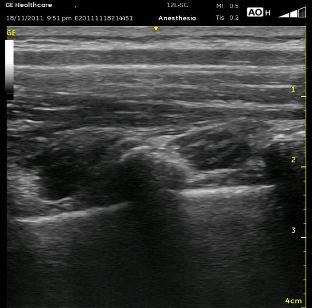

Once I have determined the sites for injection or injections, I start several centimeters laterally in a paramedian plane and follow the ribs medially. After identifying the bright shimmering white comet-tail appearance of the pleura moving with inspirations, watch for the rounded ribs to become more squared and shift slightly cranially. This is the transition from the rib to the transverse process. It can be a very subtle change. If you travel too far medially, the separated squared lines of the transverse process will become one jagged line representing the facet joints and laminae. In the series of images below (ribs, transverse processes then facet joints), the erector spinae muscles can be seen above the two layers of intercostal muscles. Cranial is to the right, and you can tell by the widening of the paravertebral space as you look from left to right.

Once you are appropriately over the transverse processes, angle the probe slightly medially (so that the beam is ‘looking’ laterally). This will allow the Superior Costotransverse Ligament (SCTL) to optimally (or at all) come into view. It is the bright white line just above the pleura in the images above. This is the critical element to recognize. This oblique maneuver is necessary to orient the probe to the ligament at a 90 degree angle because of the rounded nature of the ribs which are diving anterior (deep) as they approach each other at their posterior aspect at the spine. To see it at the most perpendicular angle, you must position the probe obliquely. As mentioned above, the SCTL will be seen going from deep to superficial as it goes caudal to cranial. That is because it attaches between the superficial aspect of the rib and the deep aspect of the transverse process cranial to it. Your goal is to put the needle just deep to the SCTL in the wedge-shaped darkened space just superficial to the pleura.